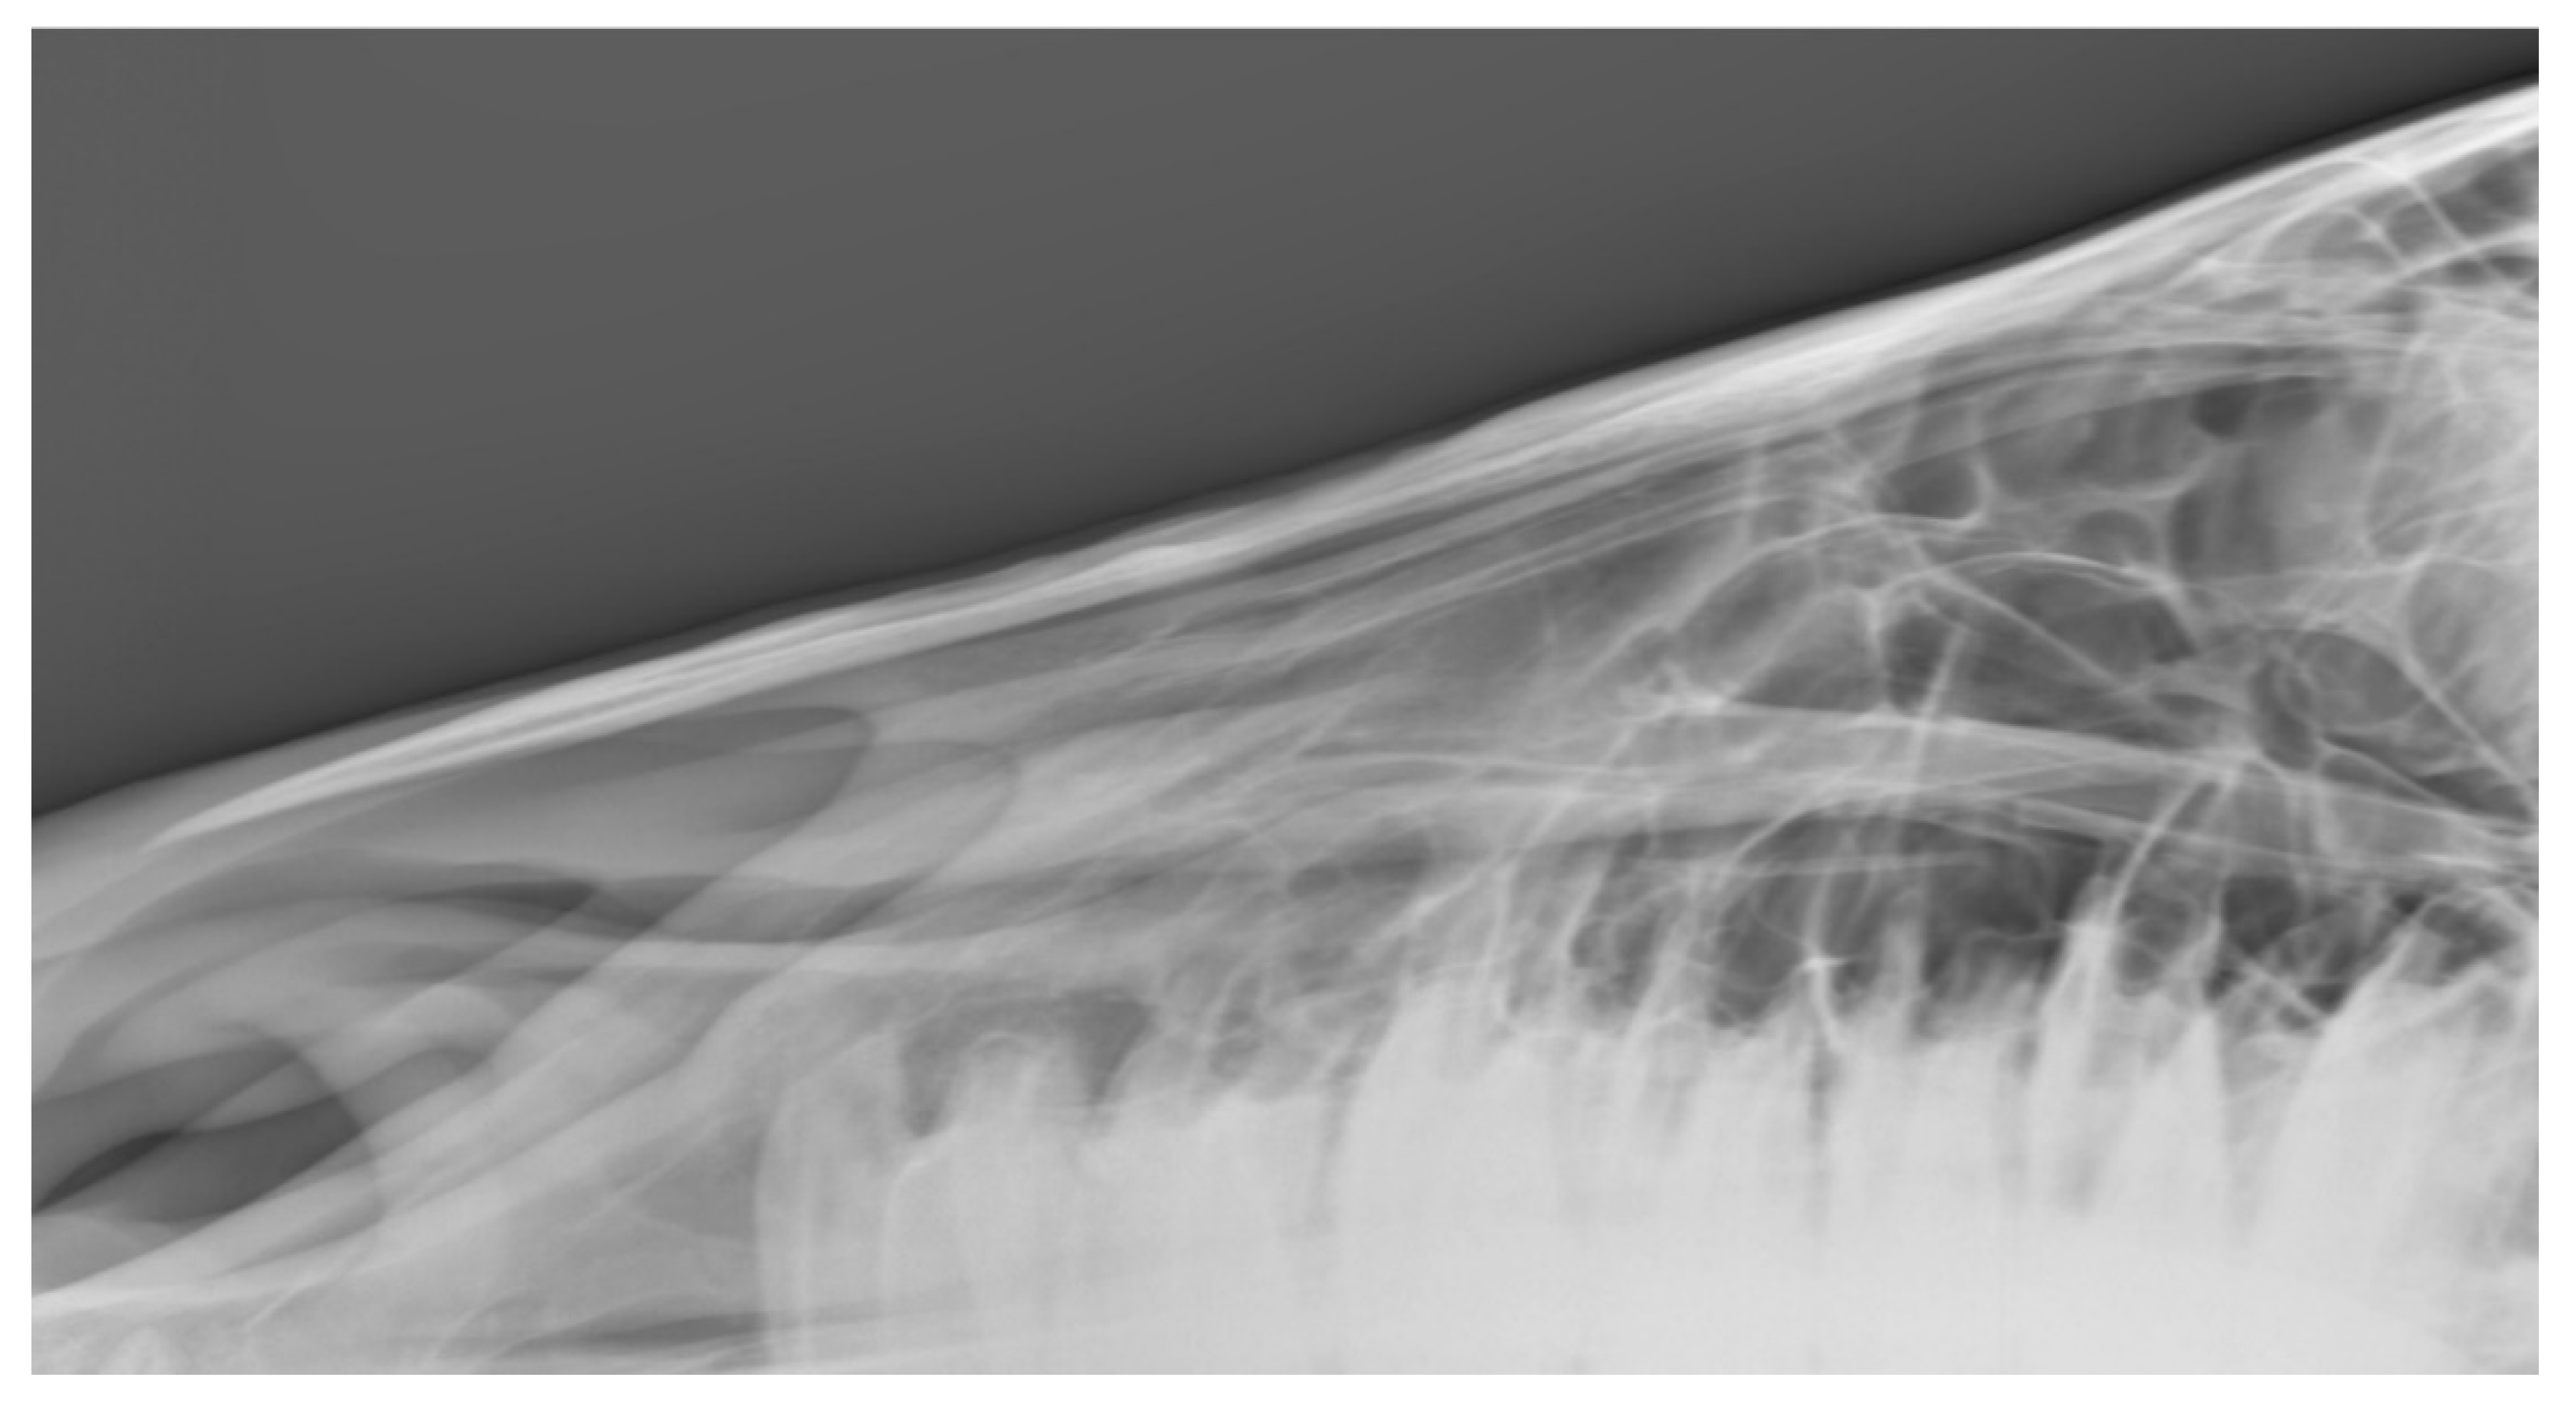

Among the 144 horses, 37.5% (n = 54) had one or more radiographic changes to the nasal bones according to both radiologists. Another 35.4% (n = 51) had no changes detected by either radiologist. For the remaining 39 horses, the radiologists disagreed about whether a lesion(s) was present. The distribution of radiological findings appears in Figure 3.

(2) Bone Thinning

Bone thinning in the nasal bone region was more commonly noted than bone deposition. At least mild change was noted by one radiologist in 33.3% of the horses (n = 48 of 144) and by the other in 56.9% of the horses (n = 82 of 144). Most change was graded mild (n = 34–59), with some moderate (n = 13–20) and a few marked (n = 1–3). Agreement was fair but somewhat lower than for exostosis with a percentage agreement = 55.6% and a square weighted Cohen’s kappa = 0.494 (z = 6.88, p < 0.001)

Figure 5. Radiographs showing the nasal bones of a horse in which radiologists (n = 2) agreed there was bone thinning that was: (a) typical of affected horses and (b) moderate.